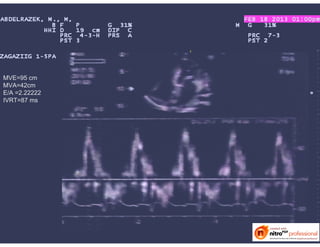

MVE=95 cm

MVA=42cm

E/A =2.22222

IVRT=87 ms

E’=0.62 cm

E/E’=16